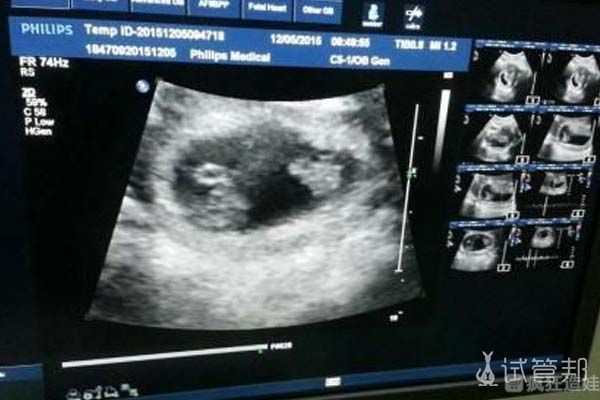

促排和取卵可能是我试管过程中最难受的阶段了,之后的培养和移植都很顺利,我移植一次成功。整个过程中,严格按照医生的要求做每一件事情对提高成功率是有很大的帮助的。其实成功的关键还是取决于男女双方身体条件。当然还会受到医院的设备和医生的水平的影响。